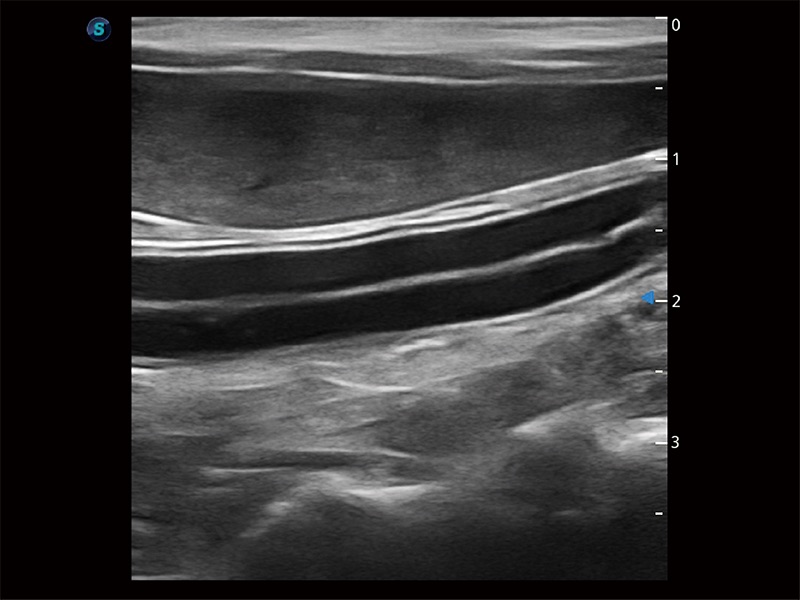

优异的基础图像

ProPet 80 全新的动物超声智能软件和丰富的探头群,为动物医生提供了高清晰度和精细分辨率的图像,无论在宠物、马科、畜牧还是实验室动物等应用中都可以轻松应对,为您的日常工作带来满意的体验。

(犬)肾脏显微血流